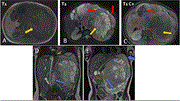

Primary Ewing sarcoma of the kidney: a rare entity with diagnostic challenges

Rihane El Mohtarim and others

Journal of Surgical Case Reports, Volume 2024, Issue 6, June 2024, rjae390, https://doi.org/10.1093/jscr/rjae390